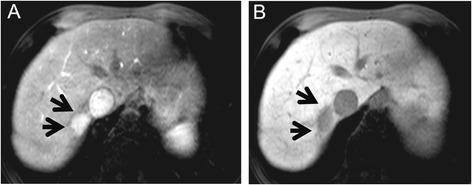

Reactive lymphoid hyperplasia (RLH) of the liver is a rare and benign nodular lesion. It remains difficult to distinguish RLH from hepatocellular carcinoma (HCC) despite recent advances in imaging modalities. We report five cases of RLH that required differential diagnosis of HCC preoperatively. These cases all occurred in middle-aged women and were associated with autoimmune disease in 40% (2/5). The diameter of the nodule was less than 2 cm in all five of our cases. Four cases had a preoperative diagnosis of HCC. When a liver nodule is found in middle-aged women with an autoimmune disease, the possibility of RLH should be considered.

肝脏反应性淋巴组织增生(RLH)是一种罕见的良性结节性病变。尽管近年来成像技术有所进步,但仍难以将RLH与肝细胞癌(HCC)区分开来。我们报告了5例术前需要与HCC进行鉴别诊断的RLH病例。这些病例均发生在中年女性中,40%(2/5)与自身免疫性疾病相关。我们所有5例病例的结节直径均小于2 cm。4例术前诊断为HCC。当在患有自身免疫性疾病的中年女性中发现肝脏结节时,应考虑RLH的可能性。